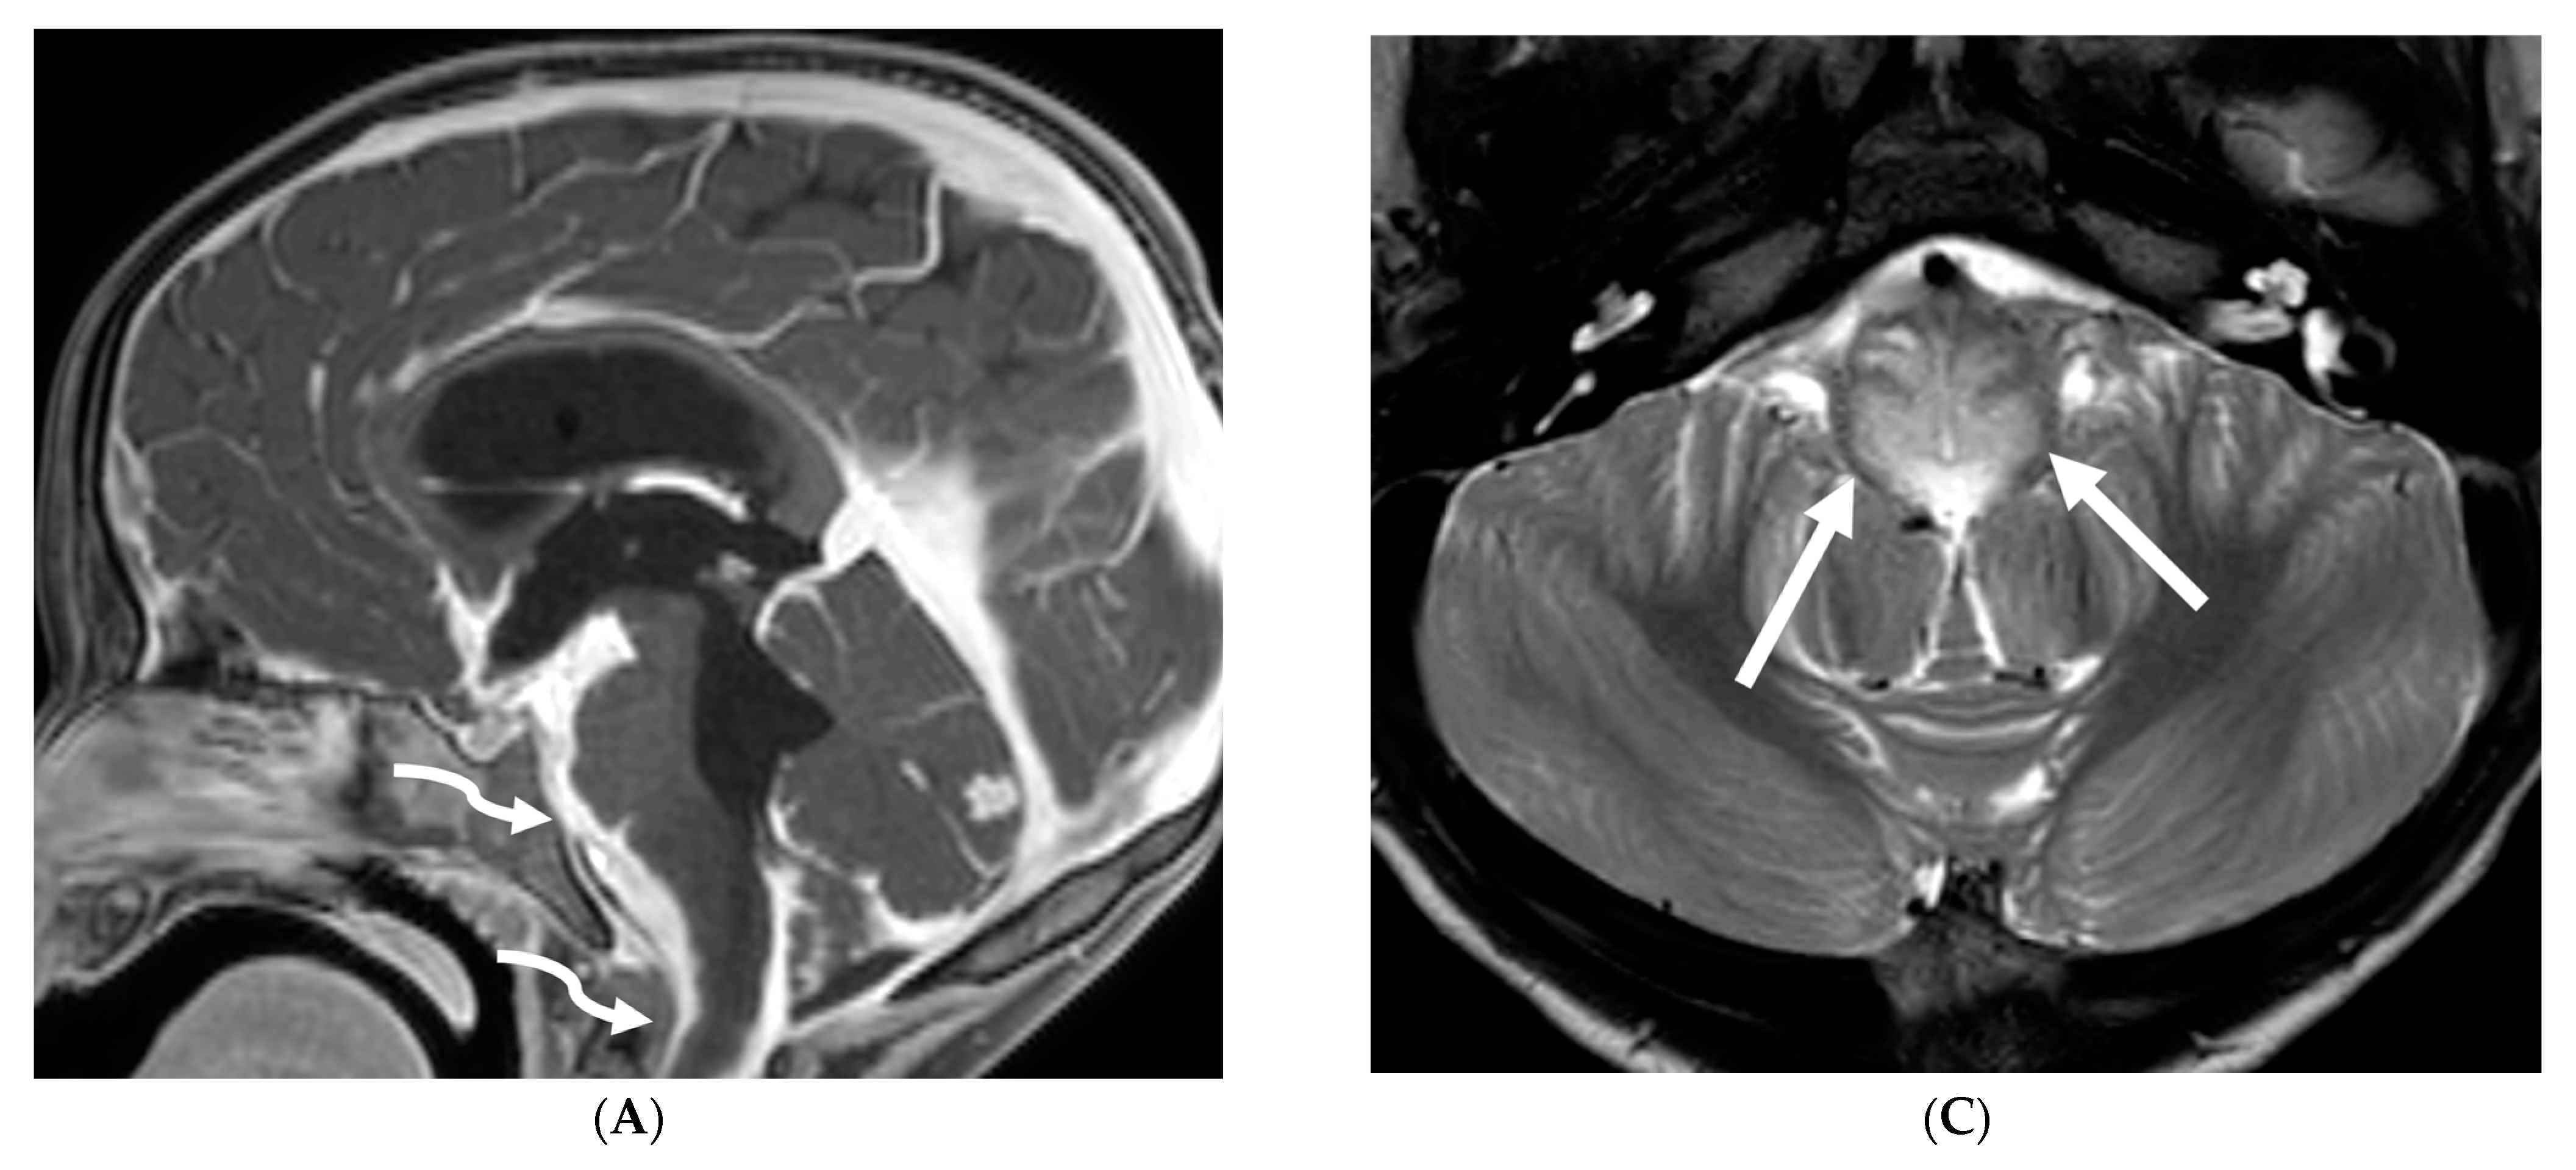

3.8. Intracranial Hypotension (IH)

Intracranial hypotension in children is frequently secondary to iatrogenic causes including lumbar punctures, craniospinal surgeries and ventricular shunt drain pressure changes [64]. Spontaneous causes are commonly connective tissue disorders such as Marfans and Ehler Danlos syndromes. Dural tears and meningeal diverticula have been demonstrated in these cases [65]. Beyond headaches, IH can manifest with nausea, vomiting, light sensitivity (photophobia), and stiff neck [66].

MRI features of IH can be explained by the Monroe-Kellie doctrine, which states that the intracerebral volume including blood, CSF and brain parenchyma remain the same. Thus, a decrease in CSF volume promotes dilatation and rounding of the venous sinuses, subdural fluid collections along with dural (pachymeningeal) enhancement which occurs due to vascular engorgement and transudation of fluid into it [67]. Hyperemia of the pituitary gland occurs which may mimic hyperplasia or pituitary tumor. Brainstem slumping or downward displacement of the brainstem, defined as red nuclei below the tentorium and low lying third ventricle below the sella, are highly specific indicators of IH, observed in half the cases. A pontomesencephalic angle of less than 50 degrees and mamillo pontine distance of less than 5.5 mm are sensitive and specific parameters to suggest IH [66].

With regard to spine imaging, in addition to the intracranial features of dural enhancement, venous engorgement and subdural collection, unique findings include meningeal diverticula, dural ectasia and C1–C2 sign (Figure 8 and Figure 9). Additionally, a CT myelogram may identify the precise location of the CSF leak which can be sealed off with a blood patch [65,68].

Figure 8.

Sagittal T1 (A), post axial T1 (B,C), axial CT myelogram (D) and technetium 99 m DTPA SPECT-CT (E): 16-year-old with Gorham’s disease. There is cerebellar tonsillar herniation and decrease in prepontine cisterns (white arrows). Significant increase in the size of the venous sinuses (dashed arrow). Diffuse pachymeningeal enhancement is seen (black arrows). Cystic-appearing foci at the skull base are in keeping with lymphangiomatosis with contrast pooling into the lytic lesion (curved arrow). Abnormal radiotracer extravasation in the left clival region correlating with lytic lesion (open arrow). Features are in keeping with intracranial hypotension secondary to CSF leak.

Figure 9.

Sagittal T2 FS (A), sagittal (B) and axial (C) T1 post contrast: 3-year-old with neck pain post LP. There is diffuse epidural thickening, with increased T2 signal and enhancement, throughout the cervical, thoracic and lumbar spine (white arrows). Several prominent flow voids are seen within the anterior epidural thickening in the upper cervical region (dashed arrow). There is also increased high T2 signal between the occiput and posterior arch of C1, and between the posterior arch of C1 and spinous process of C2 (curved arrows) in keeping with “C1–C2 sign”. Findings are related to intracranial hypotension post lumbar puncture.